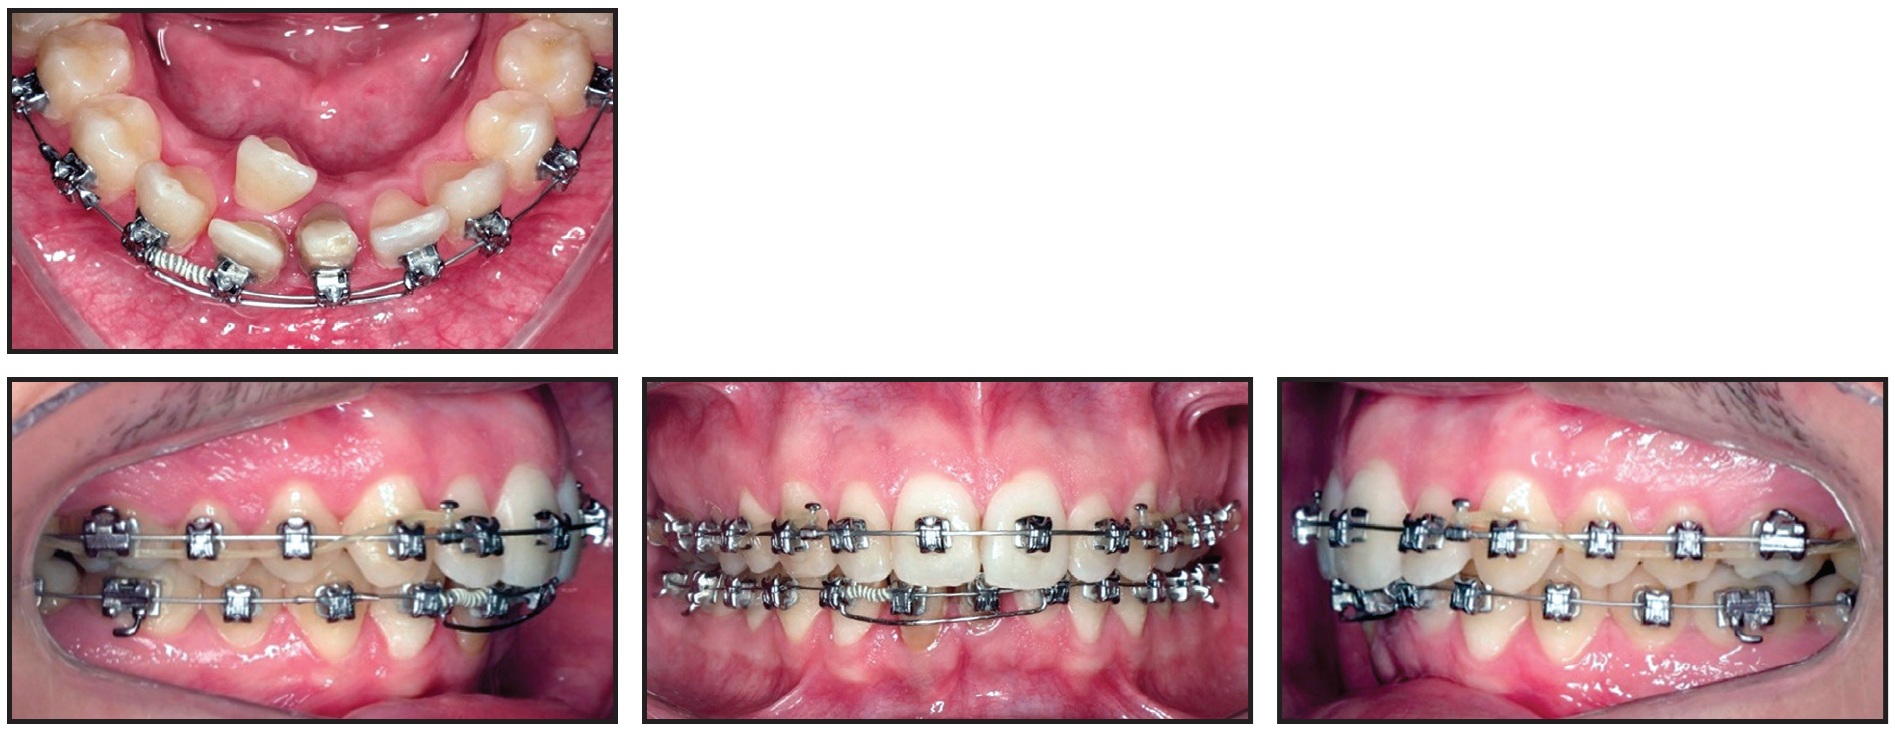

A 25-year-old male presented with the chief complaint of crowding in the mandibular anterior segment, including a complete lack of space for two mandibular incisors (Fig. 1A). He exhibited a balanced facial profile, Class I molar and canine relationships, somewhat narrow maxillary and mandibular arches, crowded upper incisors, and severely crowded lower incisors (Fig. 1B).

Fig. 1 25-year-old male patient with lower anterior crowding, Class I molar and canine relationships, skeletal Class II relationship, and severe overbite and overjet before treatment (continued in next image).

Standard-prescription .022" Damon MX* self-ligating brackets were bonded in both arches, except for the lingually displaced lower right central incisor. One month later, an open-coil spring was inserted mesial to the lower right canine on the initial .014" Copper NiTi archwire to open space for the displaced incisor (Fig. 2).

Fig. 2 Initial .014" Copper NiTi** archwire with U-shaped segmental wire in lower anterior segment.

A segmental U-shaped arch was added and slightly activated distally to control the lower incisors while avoiding any protrusion. The .014" Copper NiTi archwire was maintained for seven months, until the wire was completely passive in the slots, and was then replaced by an .014" × .025" Copper NiTi archwire. Minor interproximal stripping of the lower incisors was performed to facilitate leveling and alignment.